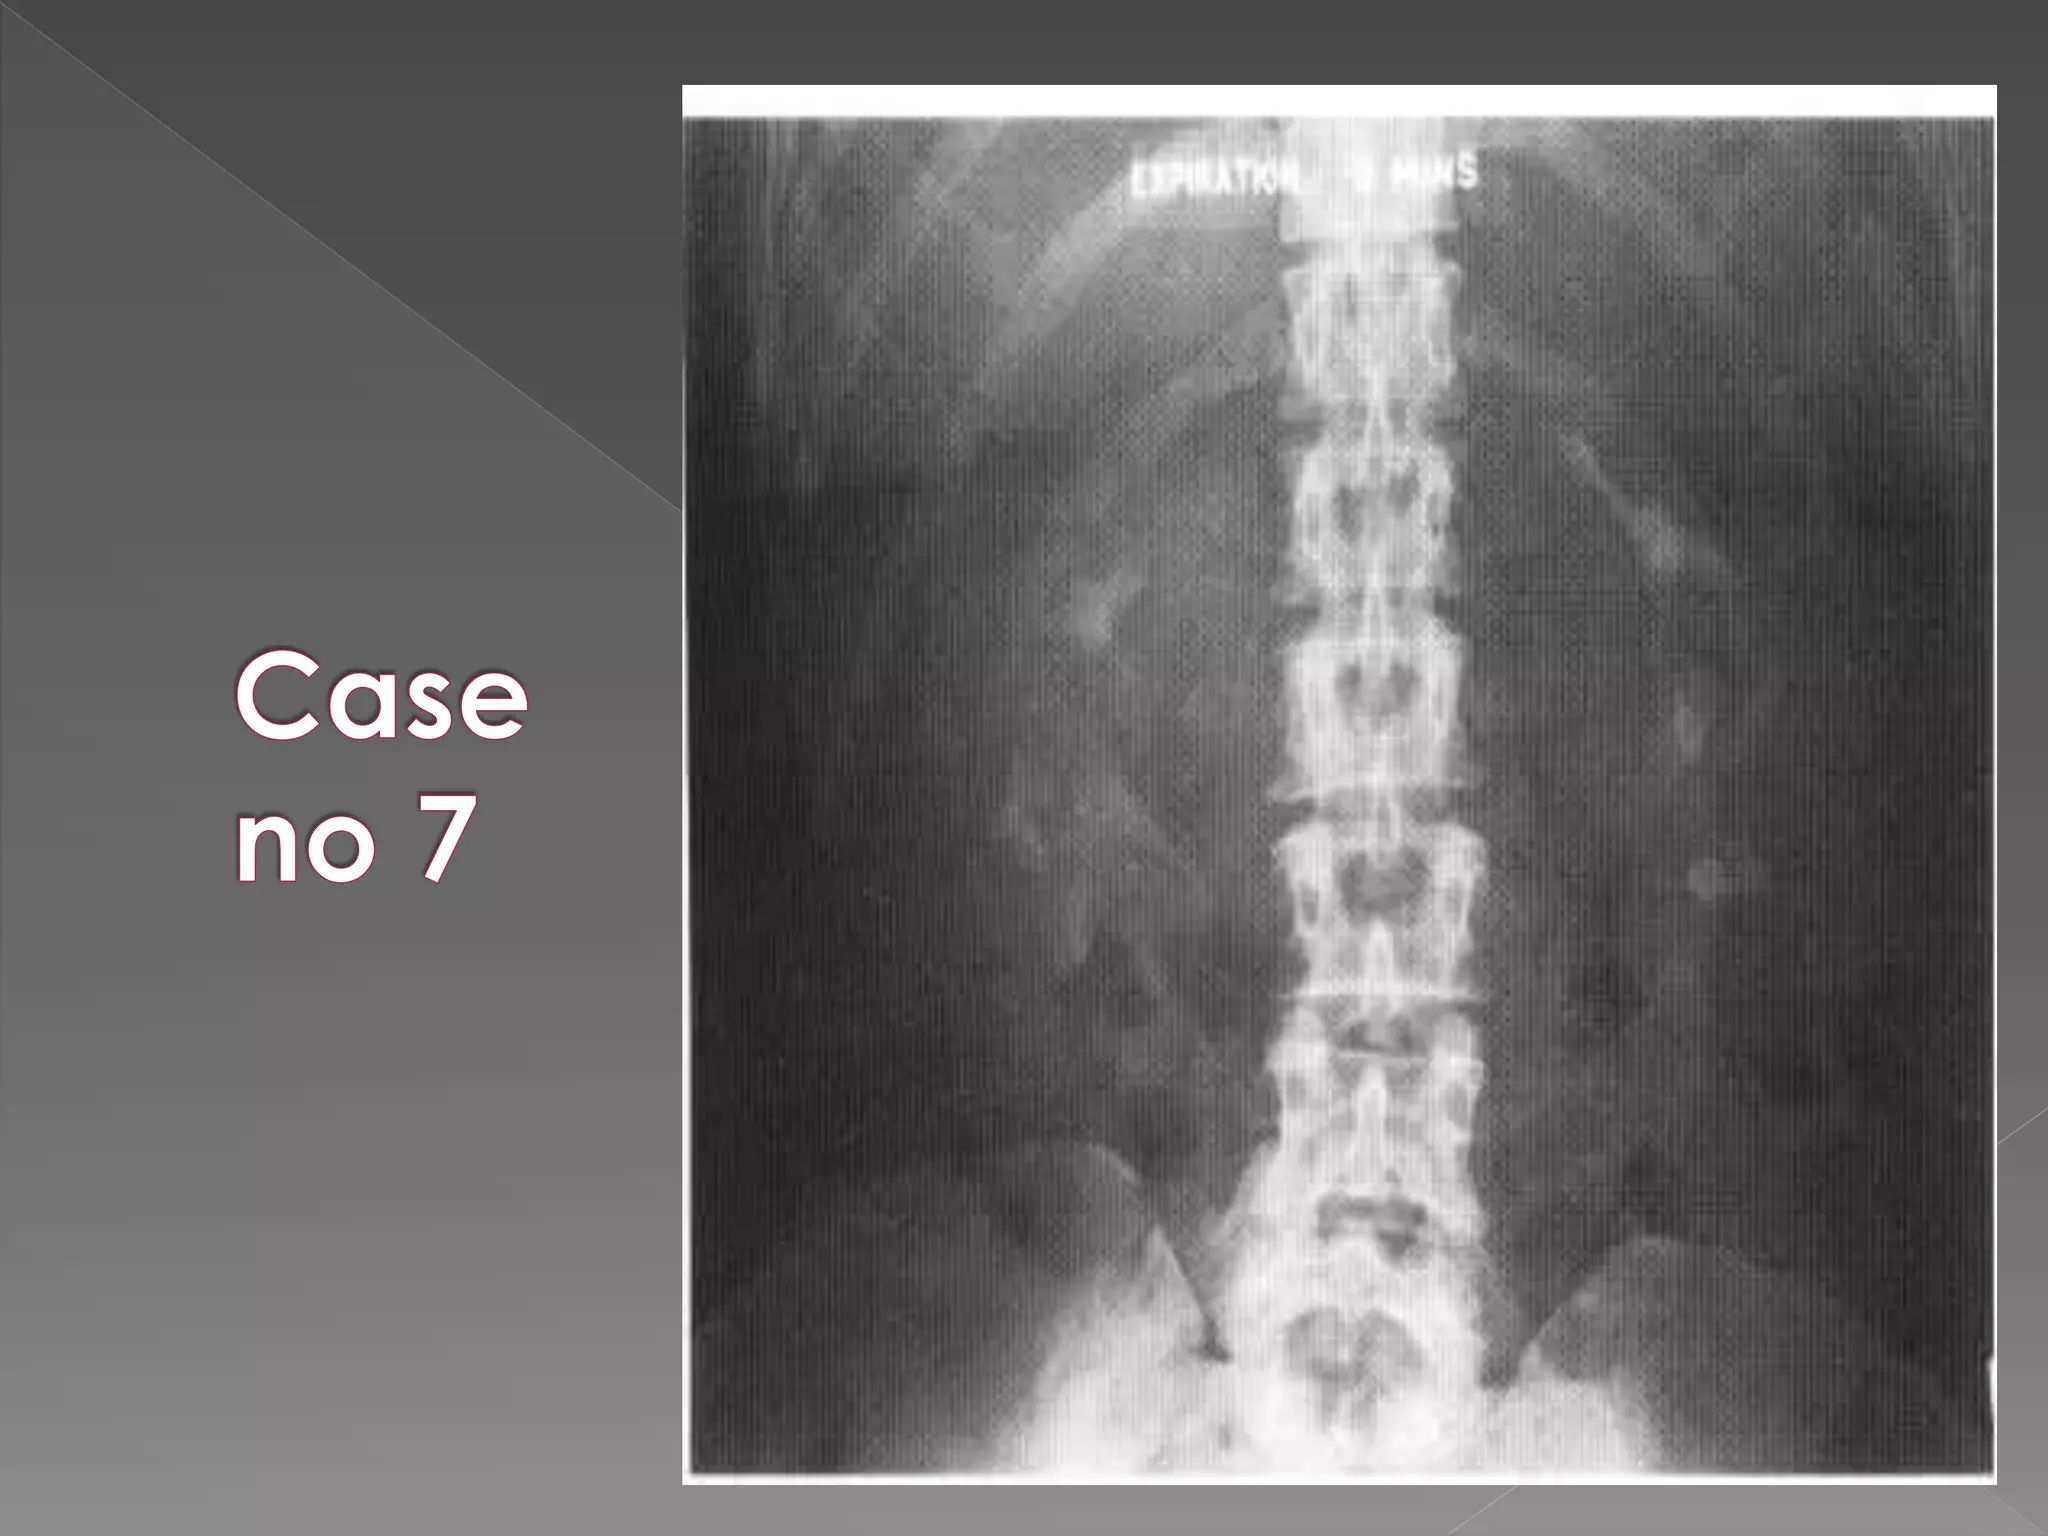

 Acute Obstruction: There is delay in opacification of the collecting system.  Delay may be considerable up to 24 hrs or more.  It is then necessary to perform additional films

 Time intervalb/w films is doubled 0.5 hrs/ 1 hr/ 2 hrs/ 4 hrs/ 16 hrs/ 24 hrs as necessary.  To minimize the radiation exposure If there is no opacification at 30 mins it is usually unhelpful to perform next film before 4 hrs